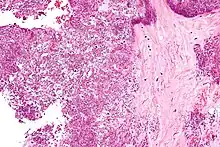

Arthrocentesis, or removing synovial fluid from the affected joint, is performed to test the synovial fluid for the calcium pyrophosphate crystals that are present in CPPD. When stained with H&E stain, calcium pyrophosphate crystals appears deeply blue ("basophilic").[16][17] However, CPP crystals are much better known for their rhomboid shape and weak positive birefringence on polarized light microscopy, and this method remains the most reliable method of identifying the crystals under the microscope.[18] However, even this method has poor sensitivity, specificity, and inter-operator agreement.[18]